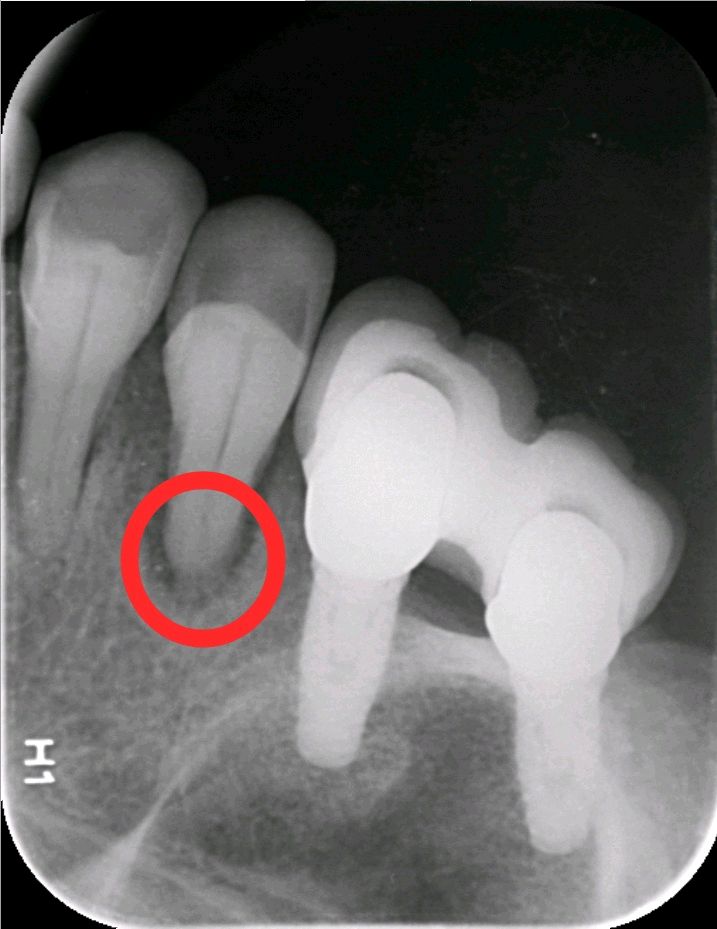

患者女,65 岁。右上 6、7 已做过两颗种植牙,因右上 5 松动,影响咀嚼,要求治疗。 口腔检查:右上 67 种植牙存,右上 5 叩诊+,探诊深牙周袋,冷热无反应,龈周-。X 线示 根尖周大面积阴影,颌面可见近远中折裂。诊断慢性根尖炎,牙根折裂。无法保留,建议拔除后,种植修复。

植入后 X 线照片